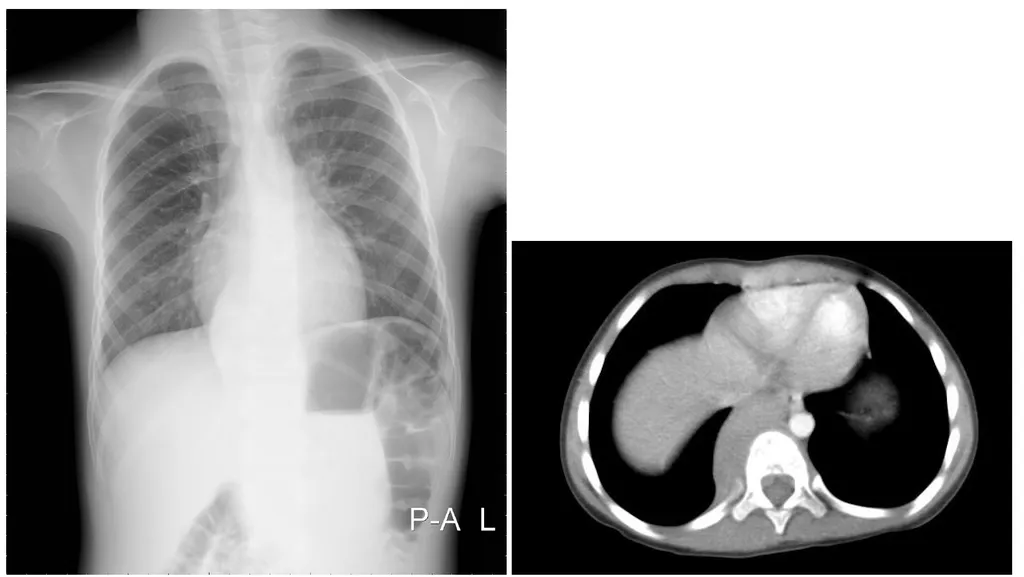

【106-1 醫學(四) 第76題】6歲女童,偶然發現胸部X光異常,胸部影像如圖,最可能的診斷為下列何者?

詳解

破題關鍵

胸部X光片顯示左側後縱膈腔有圓形腫塊陰影,而電腦斷層影像則清楚證實此腫塊位於脊椎旁,屬於後縱膈腔病灶,這在兒童中最常見的診斷就是神經性腫瘤。

選項拆解

-A:心臟腫瘤通常位於心臟內部或心包膜腔內,此影像中的腫塊明顯位於心臟外側且靠近脊椎,與心臟腫瘤的典型位置不符。